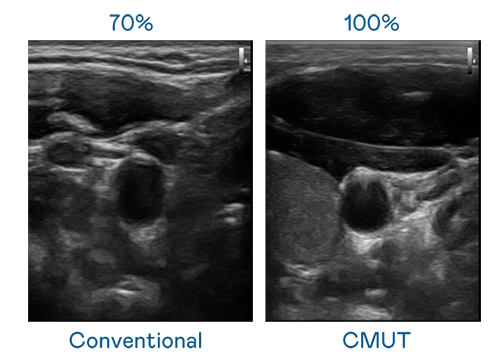

CMUT 技术是一种用电容式微机电元件来产生超音波讯号的技术。与传统 PZT 压电式技术相比,CMUT 频宽增加 30%,更宽频的超音波讯号让影像解析度大幅提升,是实现高影像品质医疗超音波扫描、促进精准医疗发展的关键技术。

大频宽带来超清晰影像

超音波影像的解析度高低,首先取决于探头能发出的讯号频宽。z6com·尊龙 CMUT 可提供高清晰的超音波讯号,提供高频宽、高灵敏度、影像纹理细节更高的超音波影像,协助医护人员缩短影像判读时间及利用精准的医疗影像进行诊断。